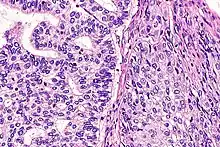

| Micrograph of a lung primary small cell carcinoma, a type of carcinoma. The clustered cancerous cells consist primarily of nucleus (purple); they have only a scant rim of cytoplasm. The surrounding pale staining, discoid cells are red blood cells. Cytopathology specimen. Field stain. | |

- Small cell carcinoma

- Cells are usually round and are less than approximately 3 times the diameter of a resting lymphocyte and with little evident cytoplasm. Occasionally, small cell malignancies may themselves have significant components of slightly polygonal and/or spindle-shaped cells.[8]